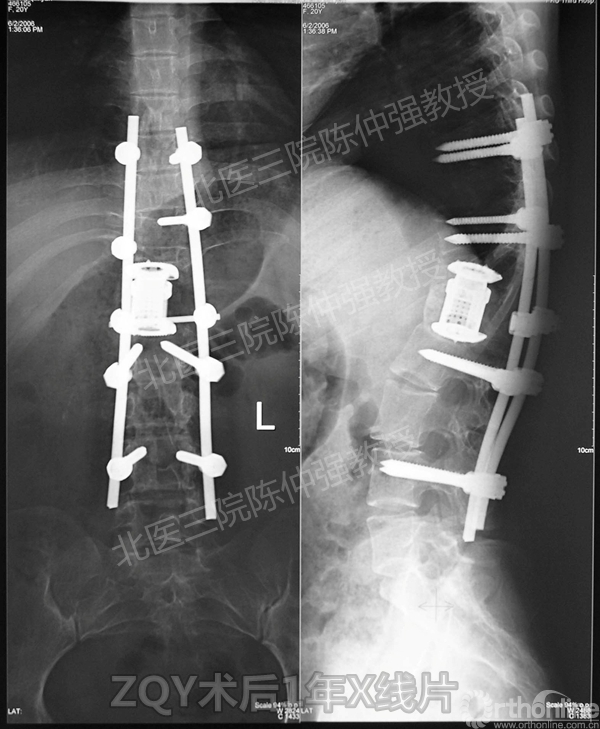

ZQY术后1

患者女性17岁,胸腰椎陈旧结核性侧后凸畸形,局部呈“麻花状”扭转,无神经功能受损表现。2005年,陈仲强教授带领团队实施后路+侧前方联合入路脊柱节段切除、双轴旋转矫形术。术后患者外观显著改善,神经功能正常。术后随访证实患者截骨矫形节段骨性融合良好,矫形效果持续良好。